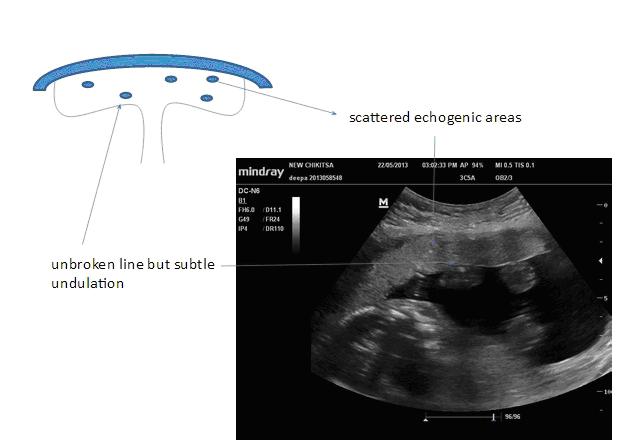

Grade - 1

It is the earliest ultrasound changes of placental maturation.

Chorionic plate - Well-defined unbroken line, but may present fine undulation.

Placental substance - Few scattered echogenic areas appear within the placenta resulting in a loss of homogeneity.

Basal layer - No basal layer echogenicities.